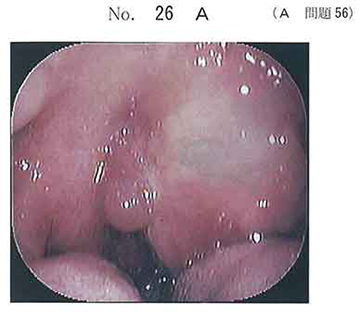

診断) 咽後膿瘍

根拠) 画像所見+炎症所見(SIRS+ 呼吸数は不明)

急性喉頭蓋炎のように,今後気道閉塞が進行するような病態ではなく,

呼吸困難の症状も無いので気管挿管は不要と考えます.